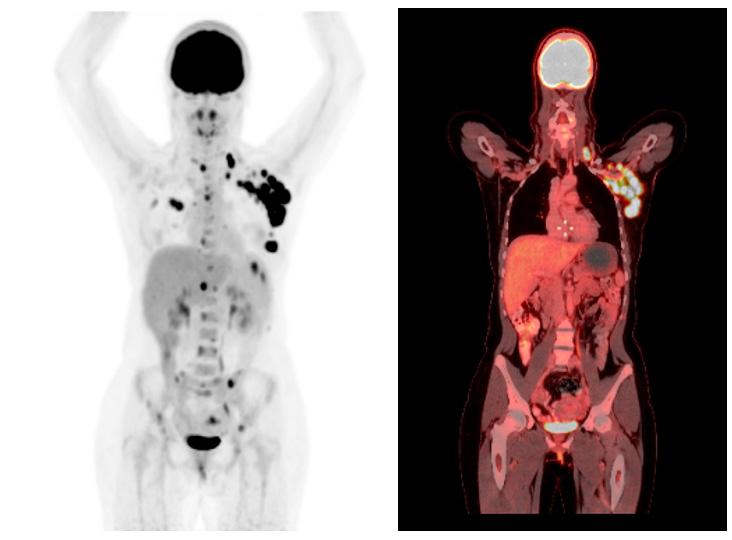

El estadio IV implica que el cáncer ha hecho metástasis a otros órganos, lo que requiere un enfoque de tratamiento más agresivo. La habilidad del PET/CT para identificar estos cambios es fundamental para los oncólogos, ya que facilita la decisión sobre el tratamiento, que puede incluir quimioterapia, radioterapia y cirugía, lo que depende del estadio y la diseminación del cáncer. “En las figuras 1 y 2” se observa un ejemplo de una paciente que acudió a la unidad, quien presentaba un estadio IIA antes del PET/CT y posteriormente cambió su estadiaje a IV, con metástasis a región axilar y ósea; contaba con subtipo molecular HER2 positivo, el cual se caracteriza por su agresividad, rápida diseminación a SNC y mal pronóstico.

Figura 1. Proyección de máxima intensidad MIP (izquierda) y PET-CT en corte coronal (derecha) en donde se evidencia actividad tumoral en mama izquierda, así como depósitos secundarios en cadenas ganglionares de región axilar izquierda, bazo y hueso